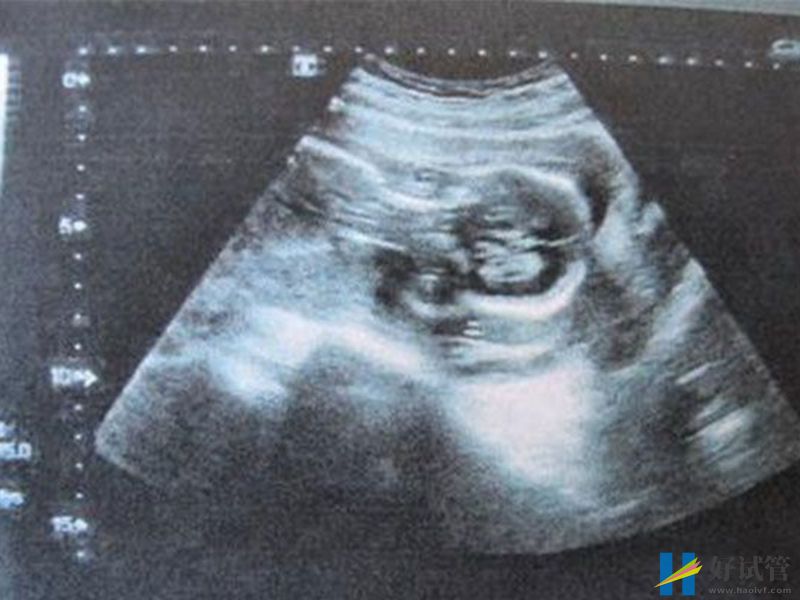

nt值2.9mm不正常!胎儿可能存在先天性疾病_好试管网